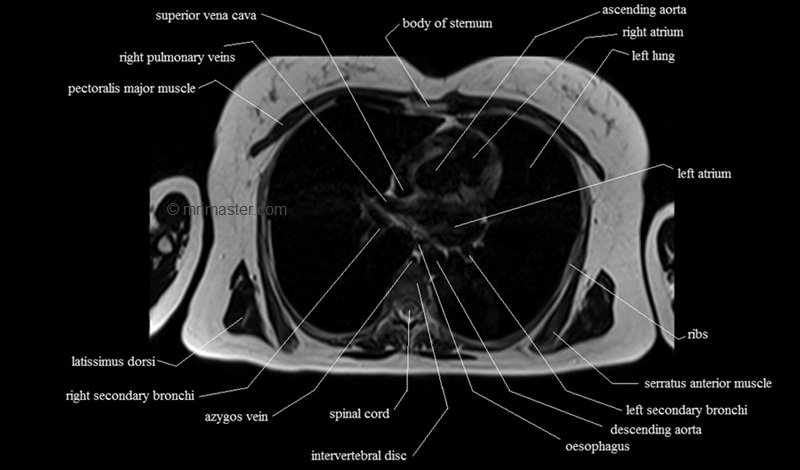

MRI Axial Cross Sectional Anatomy of Chest

This MRI chest (thorax) axial cross sectional anatomy tool is absolutely free to use. Use the mouse scroll wheel to move the images up and down, or alternatively, use the tiny arrows (→) on both sides of the image to navigate through the images. For a more detailed view, double-click the image to view it in full screen, and use the menu in the top right-hand corner to view individual slides or play them in a loop.